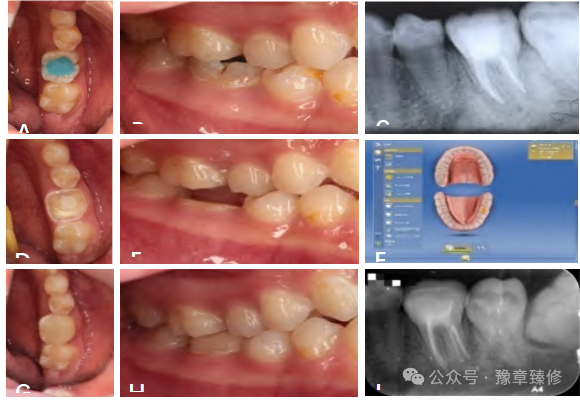

嵌体冠结合了嵌体的髓腔机械固位与冠部大面积粘接固位的优势,避免了桩道预备对根管系统的损伤[7],成为根管治疗后短冠磨牙的重要微创选择之一。其核心在于利用髓腔和剩余轴壁(高度≥1mm,厚度≥1mm,位于龈上且连续)提供双重固位(图2)。嵌体冠用于短冠磨牙时,需已完成完善的根管治疗,尤其适用于根管条件不适合桩核修复的情况(如细小、钙化根管)。短冠磨牙剩余轴壁不连续或高度<1mm(无法提供足够粘接面积)或未控制的重度磨牙症患者(侧向力易导致修复体折裂),不建议使用嵌体冠修复。

图2:氧化锆嵌体冠修复短冠磨牙备牙后及修复后A备牙后;B戴牙后;C一年后随诊;D两年后随诊